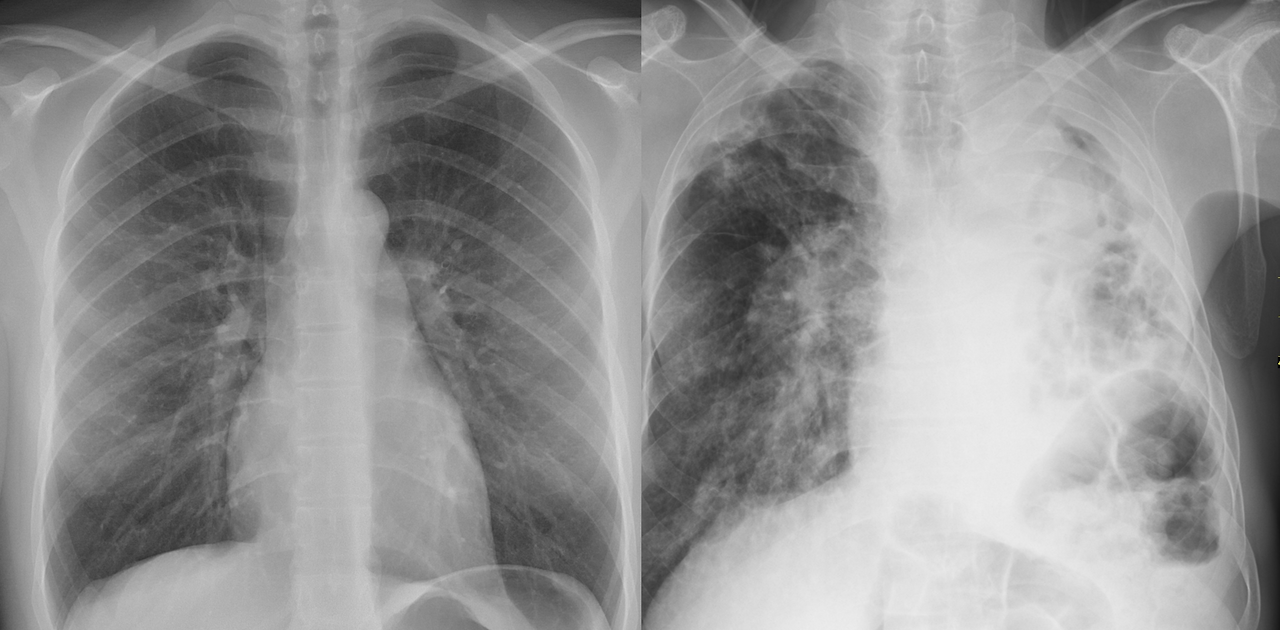

의사에게 검사는 좋다. 병원 매출에 도움이 되는 것은 물론이고, 뇌출혈, 폐렴, 충수돌기염(맹장염) 등의 대부분의 질환이 검사를 통해 진단을 내려진다. 또한 환자 상태를 설명하는 데는 백번의 말보다 한 번 눈으로 보는 것이 훨씬 낫다. 폐렴? "폐렴이 매우 심합니다."라는 말보다, 정상 사진과 하얗게 변해버린 폐 사진을 나란히 놓고 보여주면, 사람들이 모두 고개를 끄덕인다.

그림1.png <좌측: 정상, 우측: 검어야 할 폐가 특히 우측이 심각하게 하얗다. 심한 염증 소견이다. 출처: 위키미디어>